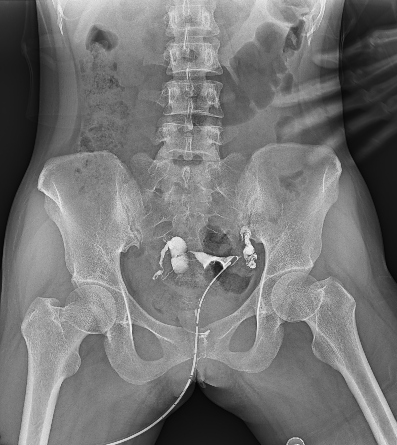

Tubal infertility is one of the main causes of female infertility. Hysterosalpingography is less invasive and can make a correct diagnosis of tubal blockage with an accuracy rate of 98% under the operation of an experienced physician.

Hysterosalpingography can understand whether the fallopian tubes are patent, the site of obstruction and the morphology of the uterine cavity according to the visualization of contrast agent in the fallopian tubes and pelvis, which is irreplaceable by ultrasound, CT, MRI, hysteroscopy, laparoscopy and tuboscopy. As the most advanced imaging equipment in the field of general radiology, multi-functional dynamic DR for hysterosalpingography greatly surpasses the past examination techniques and is more accurate, convenient and efficient.

Compared to traditional gastrointestinal machines, dynamic DR has a large rectangular acquisition area and can display the entire pelvis in a single exposure, significantly reducing observation time. Controlled transient irradiation avoids the subject from absorbing too many X-rays, which is especially important for women of childbearing age. The high-definition spot film in millisecond time can complete the film during the flow of contrast agent, capturing key images and providing a clearer picture of the specific patency of the tube lumen and the site of blockage, which is of great value for examination and diagnosis.

In addition, the use of dynamic DR for hysterosalpingography can also be useful for the treatment of some patients with mild to moderate tubal blockage by pressure pushing.

Dynamic DR can be used for a variety of gynecological examinations such as infertility, based on the advanced features of visualization of spot film and large HD format. Currently, in domestic and international medical institutions, hysterosalpingography using dynamic DR is the main method to check uterine tubal infection, and also has the therapeutic effect of separating adhesions, killing two birds with one stone. It is undeniable that the advent of multi-functional dynamic DR has further improved the level of gynecological imaging.